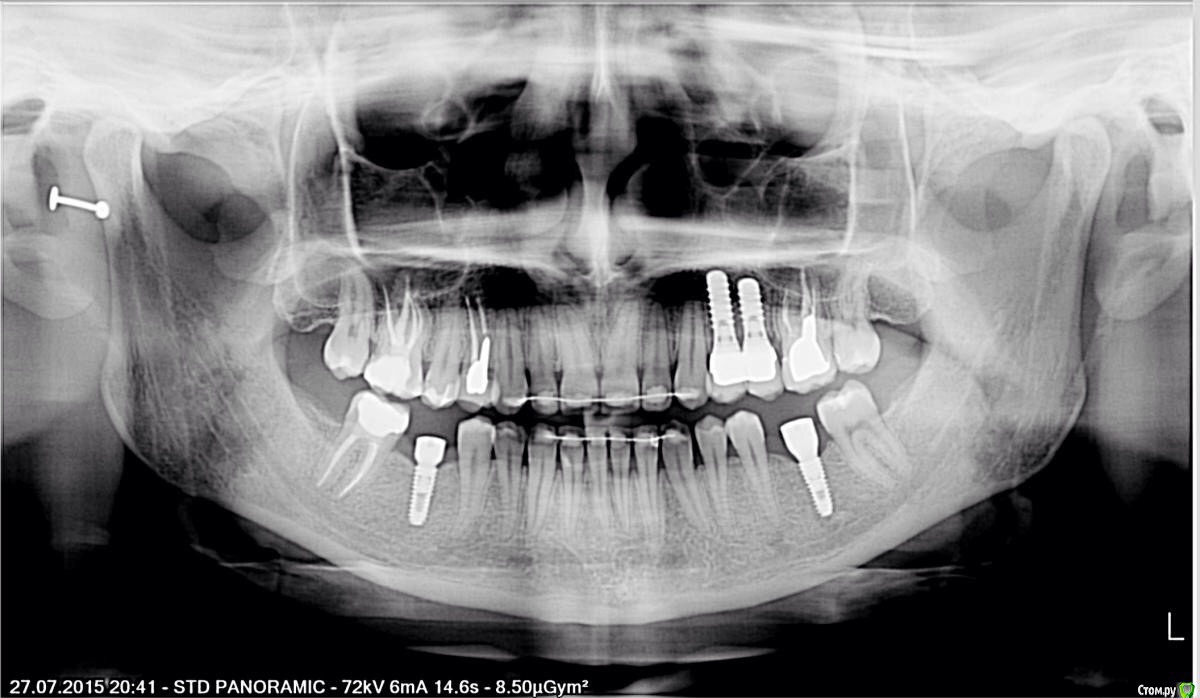

Тая.А Опубликовано 9 сентября, 2015 Поделиться Опубликовано 9 сентября, 2015 Здравствуйте, У меня вопрос по моим 2 любимым зубам, опять.4,5-импланты штрауман стандарт плюс с полированной шейкой. Нахожу все еще новые варианты, как исправить эстетику и вообще.1. Чисто гипототически: импланты стоят полгода, есть желание удалить оба, поставить вместо них астра тех поуже чтоли и БЕЗ полированной шейки, да бы эстетика была лучше. Денег нужно немерено, поэтому это в теории. Если удалять их через год например, с подсадкой костной ткани под новые имланты-насколько вероятно приживление ( 4 импланта во рту, не выпадали)? 2. Стоит ли вообще заморачиваться или результат будет не особо лучше?Это полированная шейка обернется боком потом, атрофирует кость, вылезет через десну? Ссылка на комментарий

Доктор Хаус Опубликовано 9 сентября, 2015 Поделиться Опубликовано 9 сентября, 2015 Из за того что у штрауманн платформа шире чем имплантат получается что платформы впритык к друг другу . Десна не может прорости . 1 раз прижились эти то приживутся и другие 2 я думаю можно будет достигнуть лучшего результата Если один имплантат удалить , подсадить кость потом десну и сделать временные зубы с опрой на один имплантат, создать контур десны , сделать постоянные зубы . Хотя я не особо ставил штрауманн , не знаю их особенностей.Все это мои домыслы , если что коллеги поправьте. Ссылка на комментарий

Bier Опубликовано 10 сентября, 2015 Поделиться Опубликовано 10 сентября, 2015 если удалить оба имплантата - есть риск получить приличную атрофию кости. Потом будет не просто все вернуть.Чтобы вести речь о двух новых имплантатах - нужно очень тщательно все измерить. вот пример работы, где на одном имплантате 2 зуба. 2 имплантата убили бы все.http://img-fotki.yandex.ru/get/9172/40752090.6/0_c8c1c_8eb1afb1_orig.jpg 3 Ссылка на комментарий